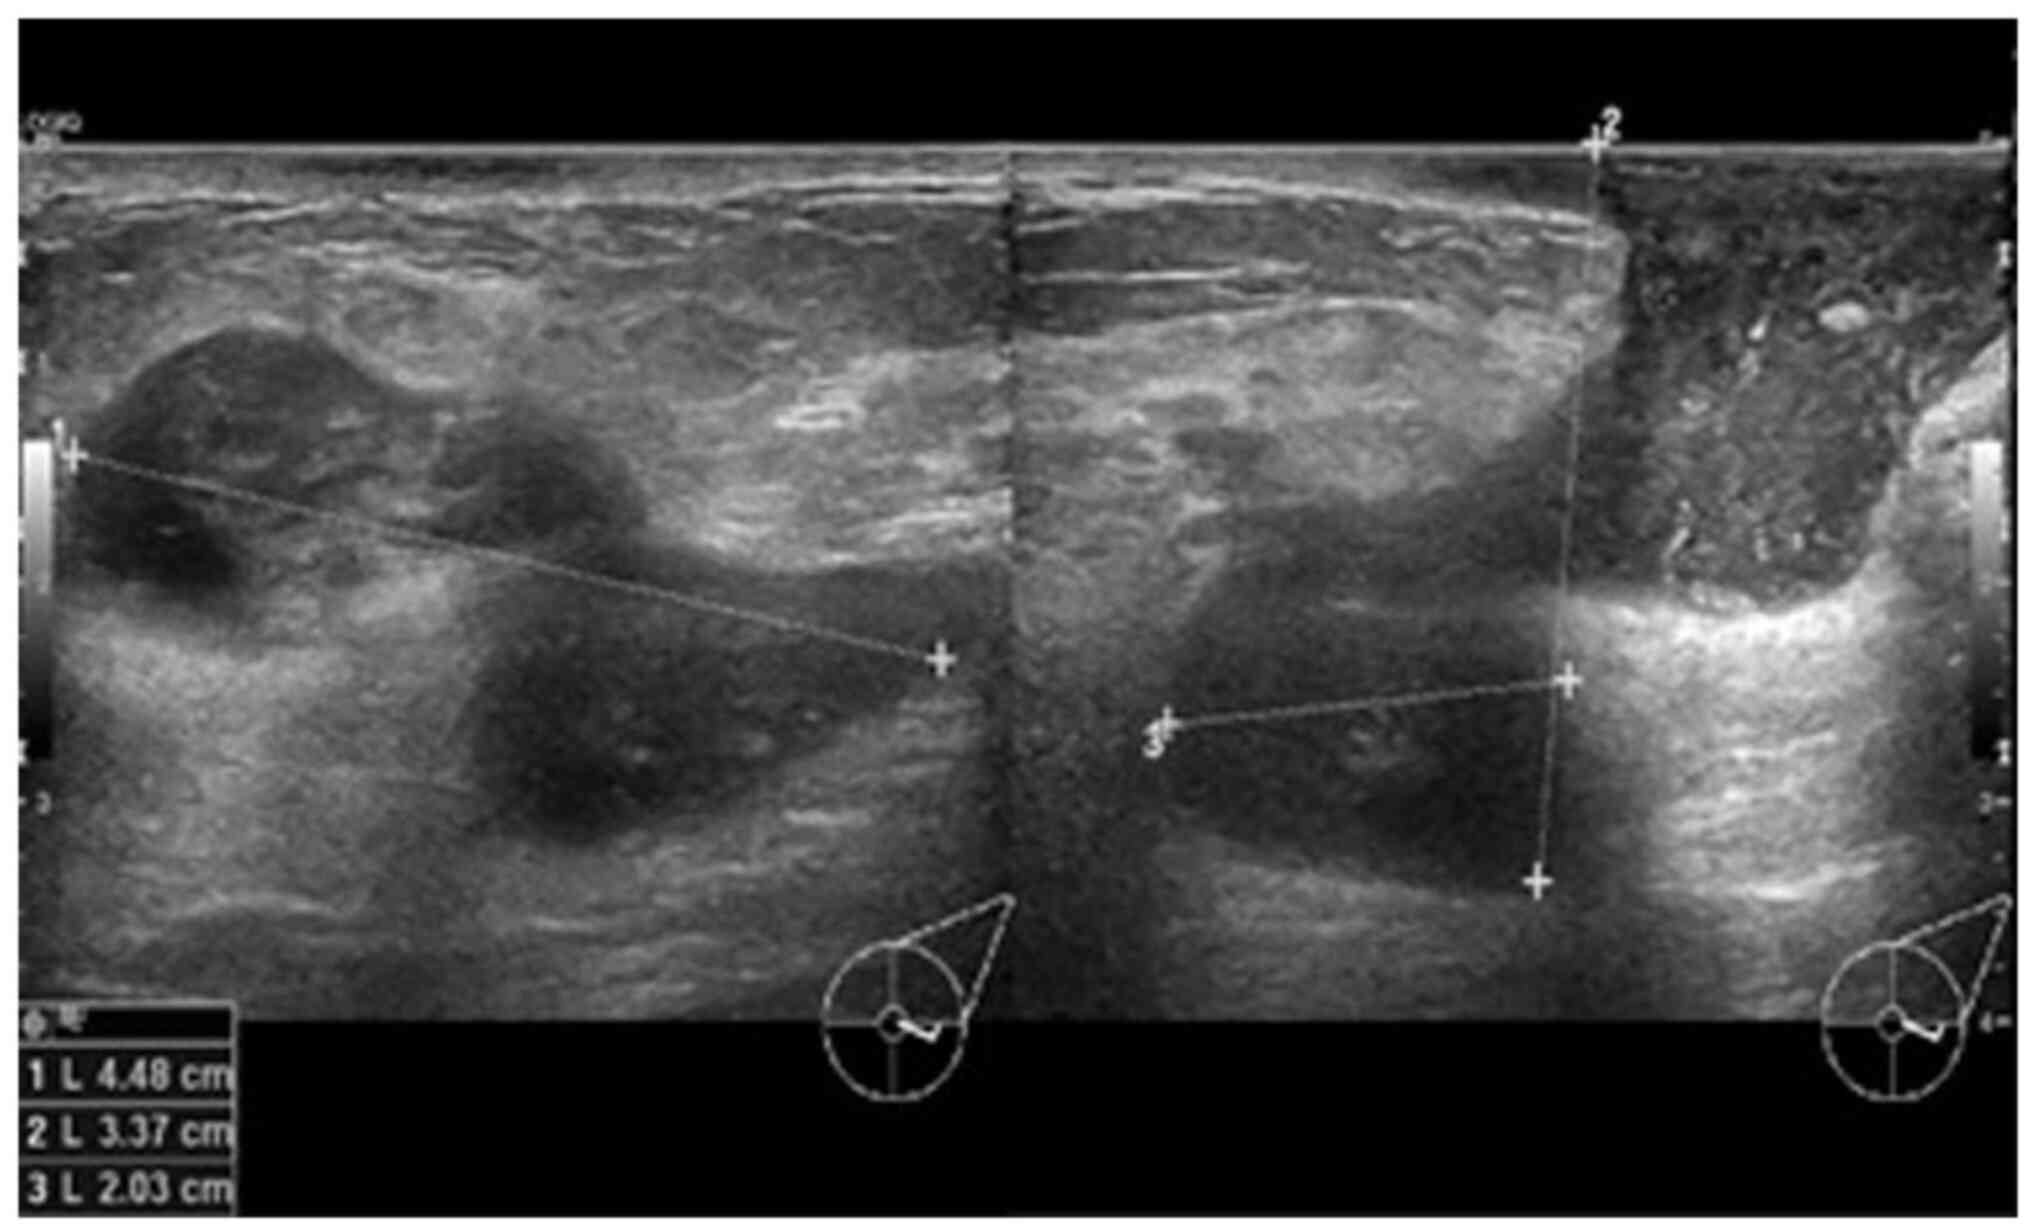

In view of the persistence of the mass, a breast ultrasound was performed. The initial examination yielded normal results. A second ultrasound repeated after 10 days (Fig. 1) revealed an area of architectural distortion with dilated ducts measuring up to 0.3 cm in diameter located at the 3 to 4 o'clock position of the left breast. There was no discrete mass or significant axillary lymphadenopathy. The findings were consistent with mastitis. The other differential diagnosis was inflammatory breast carcinoma. The patient was treated with a course of oral Augmentin (amoxicillin and clavulanic acid) and although the swelling decreased in size, it did not completely resolve. A third ultrasound (Fig. 2) after 2 weeks of treatment was suggestive of a 1.3-cm hypoechoic mass with indistinct borders at the 4 0'clock position. A decision was made to proceed with a biopsy. A repeat ultrasound (Fig. 3) was conducted after 6 months, which revealed hypoechoic tubular collections and fistulous tracts towards the skin.

Figure 2

Ultrasound images illustrating transverse (right panel) and longitudinal (left panel) views of a hypoechoic mass with indistinct borders after 2 weeks of treatment with antibiotics.

The case described herein was a nonlactating multiparous woman of 32 years of age, which fits the demographic profile for idiopathic granulomatous mastitis (12). The radiological findings in this patient included architectural distortion, with dilated ducts in the pre-treatment breast ultrasound and a hypoechoic mass with indistinct borders post-treatment with antibiotics. Radiological findings in CNGM have been sporadically reported in case reports and case series, and include a spectrum of findings (1,13). A mass is the most common radiographical feature followed by dilated ducts (1). Edema with no mass, abscesses and sinuses are also observed. The majority of cases are reported as Breast Imaging-Reporting and Data System (BIRADS) score 4 (suspicious). Malignancy is often suspected based on the finding of an irregular or ill-defined hypoechoic mass with shadowing observed on a breast ultrasound (13). The finding of a hypoechoic mass with indistinct borders in the case described in the present study is congruent with the reported radiological findings for granulomatous lobular mastitis (GLM) and CNGM (1,13,14). The literature reviewed from case reports and series has documented one radiological finding per patient. To the best of our knowledge, the present study describes the first case documenting radiological findings before and after treatment (1,13). The spectrum of findings reported for the case described herein, including dilated ducts followed by a mass and then fistulous tracts suggests a progression of the disease, despite therapy. The initial finding of dilated ducts was consistent with mastitis; however, the presence of a mass despite antibiotic therapy necessitated biopsy in this patient in order to exclude neoplasia. Inflammatory breast carcinoma was considered as a differential diagnosis for this case. Both inflammatory breast carcinoma and GLM can reveal hypoechoic masses and the ultrasound findings of the two can overlap such that biopsy of the lesion is required for a definitive diagnosis (14).